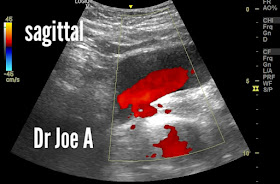

- Ultrasound imaging of the urinary bladder may reveal a "ureteral jet".

- A ureteral jet appears as a small, pulsatile stream of urine entering the bladder.

- It indicates the presence of normal, unobstructed flow from the ureter to the bladder.

- Ureteral jets can be visualized using color or spectral Doppler ultrasound.